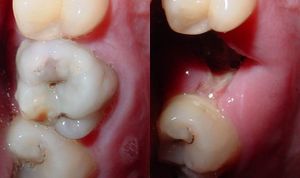

| Destruction of a tooth by cervical decay from dental caries | |

هو تخرب يصيب نسج السن الصلبة بدءاً من طبقة الميناء enamel ثم يصل إلى طبقة العاج محدثاً حفرة قد تزداد اتساعاً وعمقاً لتصل إلى اللب الذي يحتوي الأوعية الدموية والأعصاب.

حدوث التسوس وتطوره

تقوم الحموض الناتجة من عملية تخمر السكاكر بحل العناصر المعدنية والعضوية التي تدخل في تركيب ميناء السن فتبدو المنطقة بيضاء طبشورية وذات ملمس خشن. ولدى تزايد إنتاج الحموض وعدم تطبيق الفلوريد الموضعي على الأسنان الذي يقوم عادة بإيقاف تطور التسوس، يتهدم الميناء وتصل الإصابة إلى العاج مشكلة حفرة التسوس التي يمكن ملاحظتها سريرياً ويبدأ الإحساس بالألم لدى التعرض إلى مؤثرات خارجية من سخونة وبرودة أو الضغط أثناء المضغ. عند إهمال معالجة التسوس في هذه المرحلة يزداد التخرب وتصل الإصابة إلى لب السن الذي يصاب بالالتهاب وترافقه موجات حادة من الألم وخاصة في أثناء الليل. إن عدم تطبيق المعالجة الملائمة في هذه المرحلة يؤدي إلى تموت اللب وإصابته بالتعفن وتتكون الخراجات الحادة والمزمنة والآفات الذروية التي تنتهي بقلع السن المصابة.